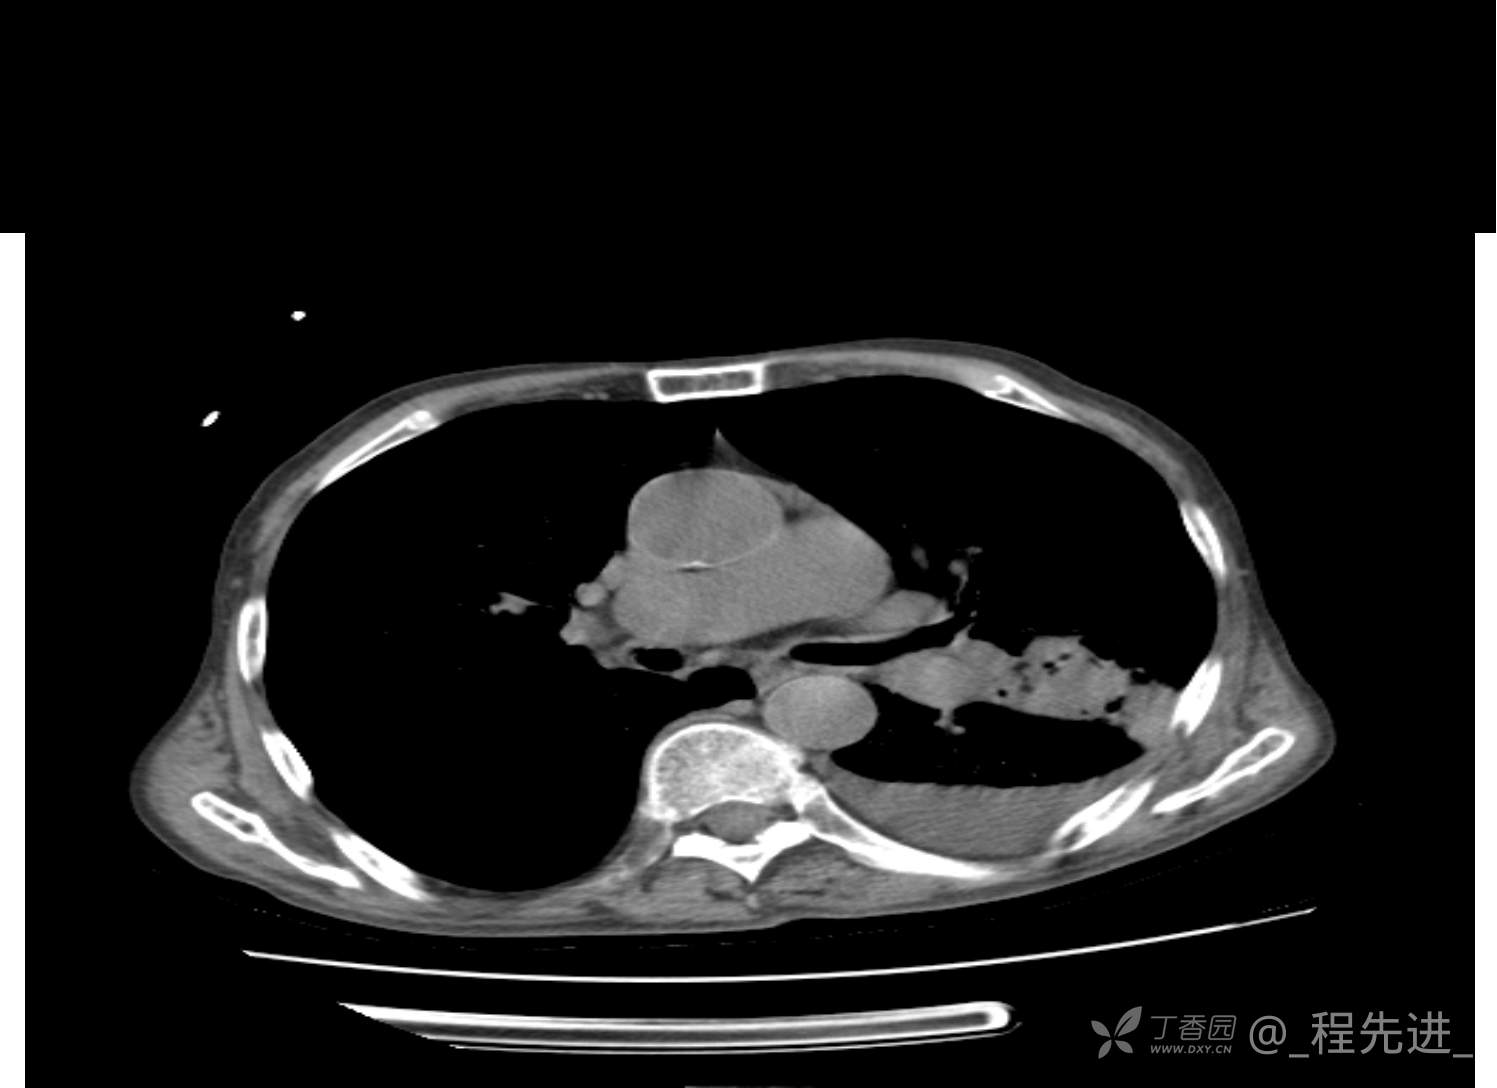

患者性别:男

患者年龄:81岁

简要病史:反复咳嗽、咳痰20余年,加重1周。两肺呼吸音低,可闻及散在干湿啰音。